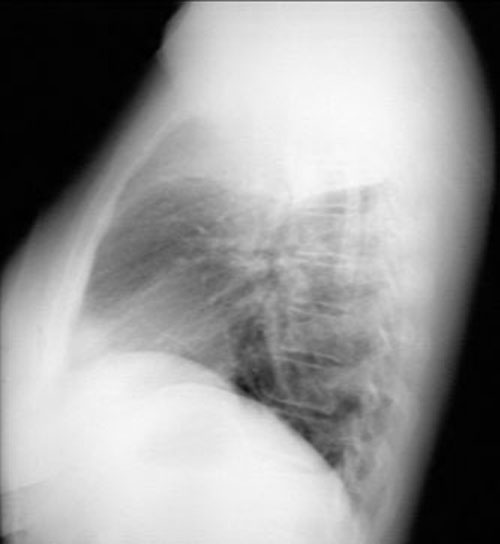

Right upper lobe consolidation

• Density in the projection of right upper lung field

• Upper lobe distribution

• No significant loss of lung volume

• Air bronchogram